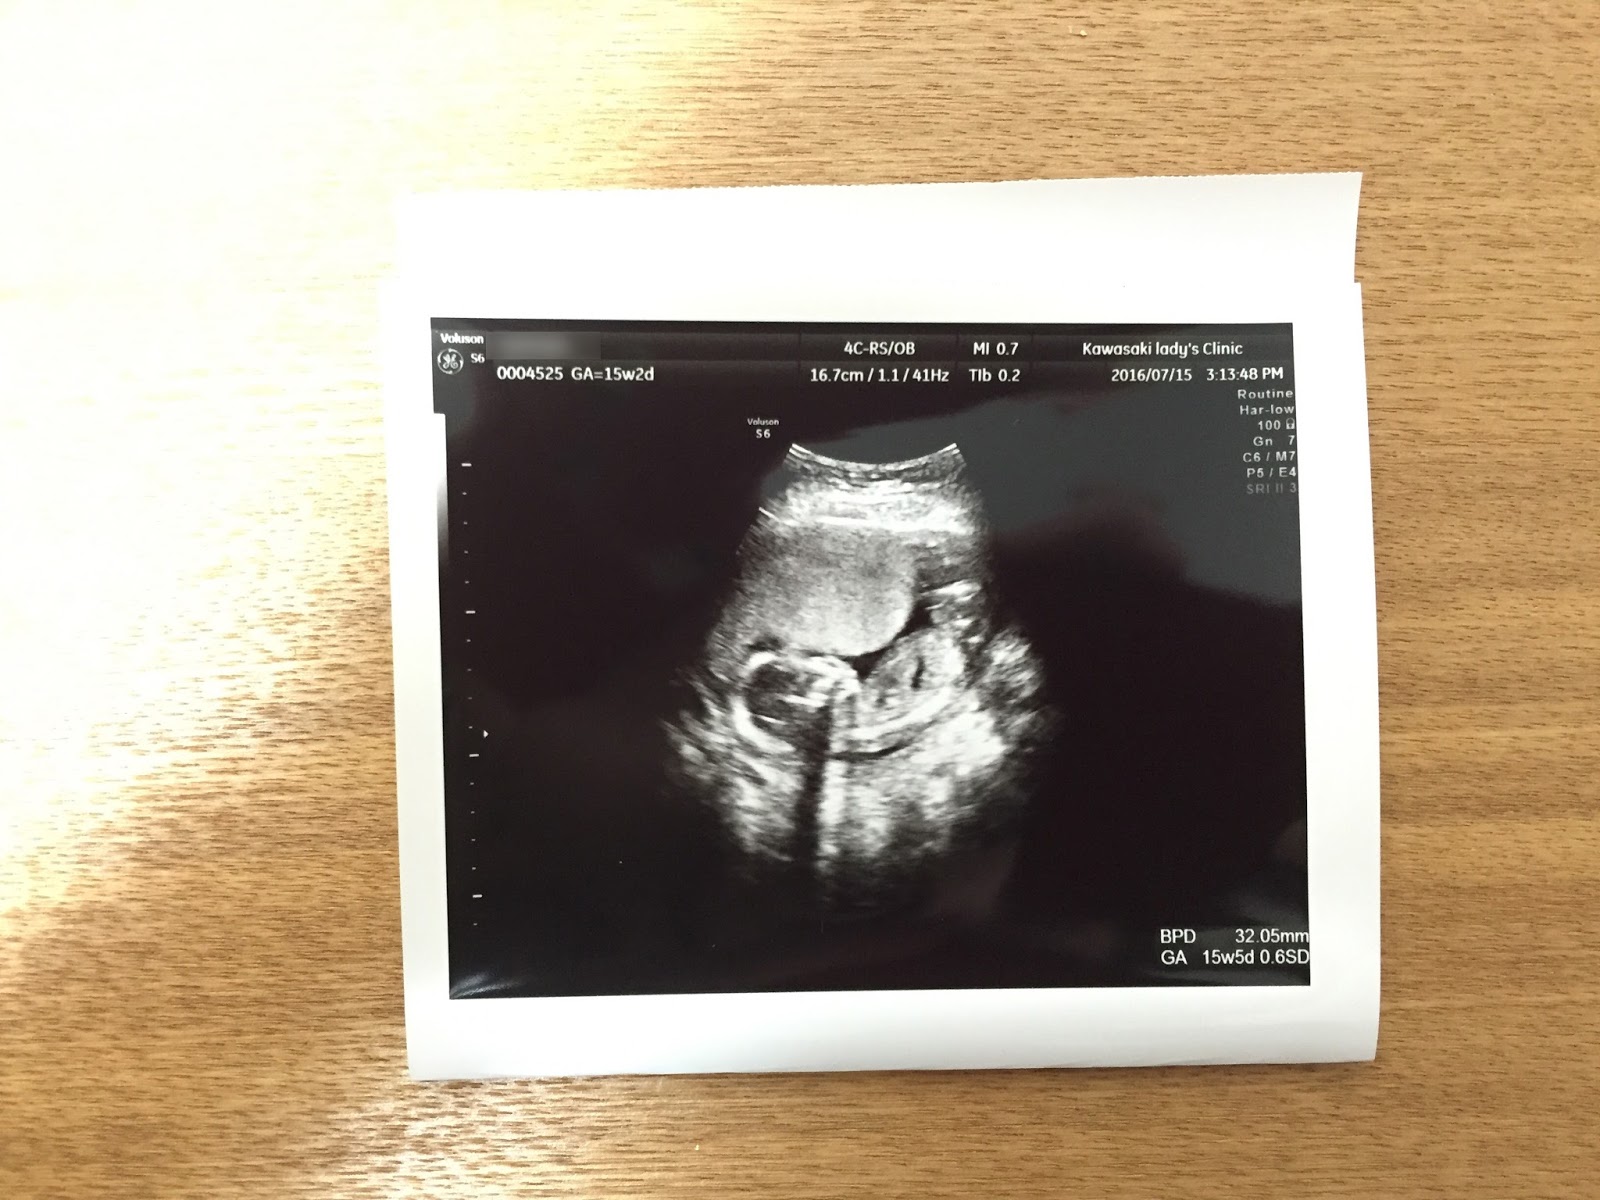

7/15の検診にて撮ってもらったエコー。↑

元気にモニョモニョ。

7月20日で16週目 (5ヶ月)に無事入り